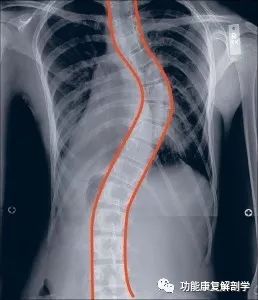

儿童脊柱侧弯的早期识别

治疗脊柱侧弯常常让人感觉像是在和一个比自己领先的对手赛跑。一旦脊柱侧弯的曲度开始发展,父母和医生很容易陷入到应对防止曲度发展的反应当中。

不幸的是,我们对儿童脊柱侧弯的治疗往往只是围绕着一个单一的焦点—预防侧弯曲度的发展,而并没有充分考虑到儿童长期的生活质量。虽然传统的治疗方法可以达到一些初期曲度减少的效果,然而从儿童一生的长远过程来看,它们也会给孩子们造成重大的伤害。比如,当我们最关注的是如何避免曲度达到外科手术的程度的时候,支具似乎是当下最好的措施,但是从25年后或者50年后来看呢?